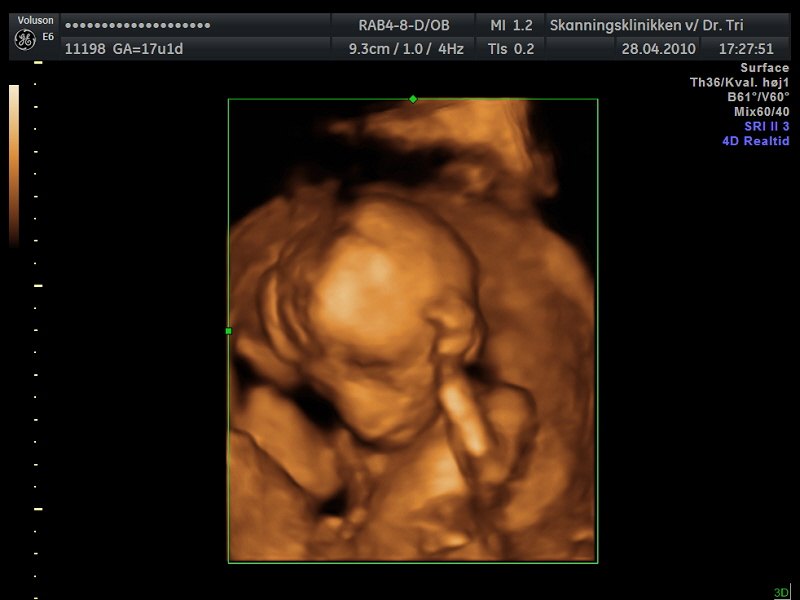

Desværre lå moderkagen foran så billederne blev ikke ret gode men her er et par stykker:

Min moderkage ligger nemlig også foran, men syntes stadig at billederne er helt fine